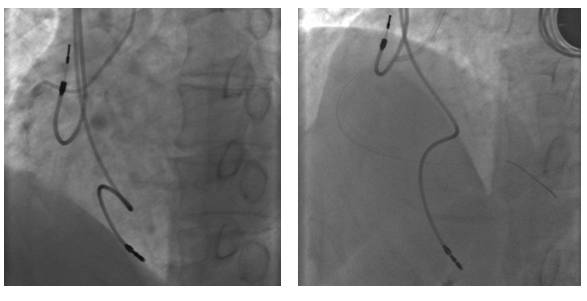

2016-12-4PCI术后植入临时起搏器

冠脉造影结果

冠脉造影结果(右冠)